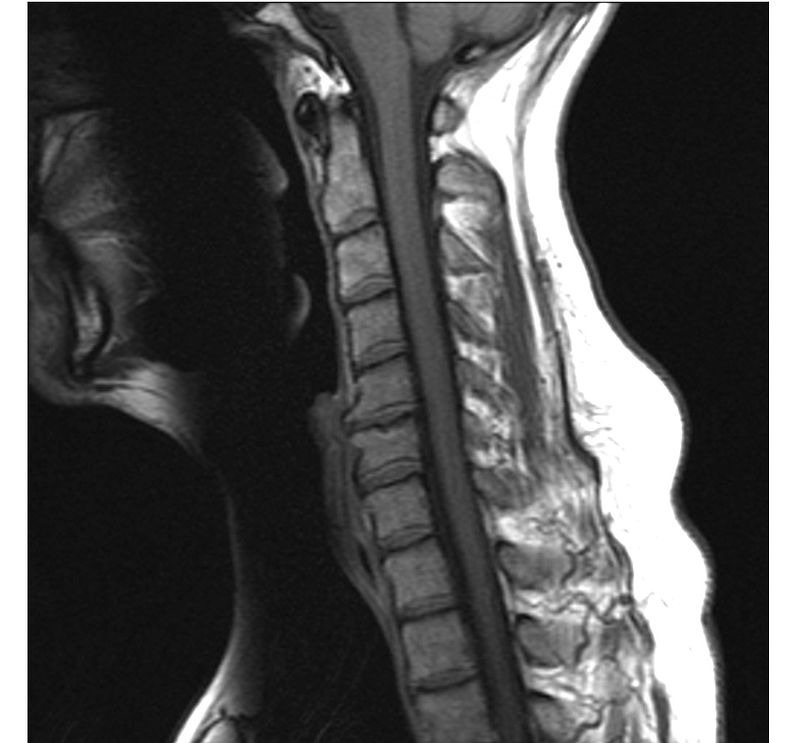

CERVICALGIA: COME CURARLA? La cervicalgia rappresenta uno dei disturbi muscolo-scheletrici più comuni. Essa riguarda la percezione di dolore tra la base della nuca e l’ultima vertebra cervicale. I due terzi della popolazione soffrono di cervicalgia ed una minoranza soffre di disturbi secondari neurologici come formicolio al braccio e alla mano. La debolezza dei muscoli flessori craniocervicali e la postura anteriorizzata del capo sembrano costituire le principali cause della sua insorgenza. Se si aggiungono poi tutti gli eventi traumatici che incidono sul collo, le degenerazioni osteo-articolari delle vertebre e dei dischi intervertebrali, capiamo come è complessa, a volte, la causa scatenante dovendo intervenire in diversi modi. Oggi esiste una nuova causa che si riscontra già tra gli adolescenti e riguarda l’utilizzo di smartphone e dispositivi simili. L’utilizzo di questi apparecchi ci porta ad assumere una postura del capo e delle spalle ricurva, creando scompensi che con il passare del tempo diventano cronici e portano addirittura a danni importanti a livello cervicale. Una volta risaliti alla causa, ecco l’importanza della visita, si interviene con la cura fisioterapica, che comprenderà una serie di atti volti a risolvere le varie problematiche. Nel migliore dei casi, basterà eseguire una serie di esercizi mirati a rinforzare i muscoli per poter eliminare il dolore completamente. Nei casi più complessi, si interviene con l’aggiunta o esclusivamente con elettromedicali di elevata efficacia, disponibili presso lo studio fisioterapico Daniele a Pescara dove si esegue la terapia del dolore per la cura di patologie anche di grave entità. E’ bene intervenire subito evitando così che si produca un danno permanente.